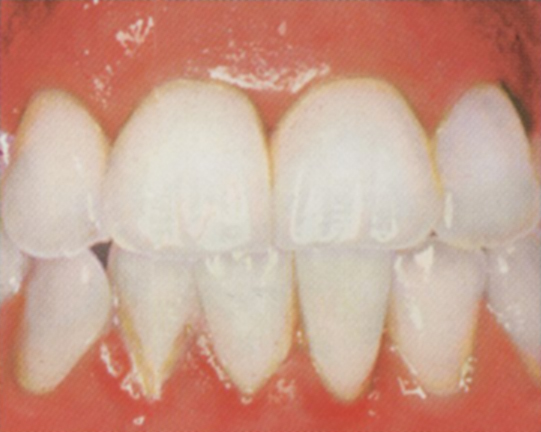

Počáteční parodontitis obr. 3

- dásně jsou červené, oteklé

- krvácení při čištění je výraznější

- zápach z úst

- sondovatelná hloubka dásňového žlábku se prohlubuje na 3-4 mm

- na rtg je patrný úbytek horizontální úbytek kosti